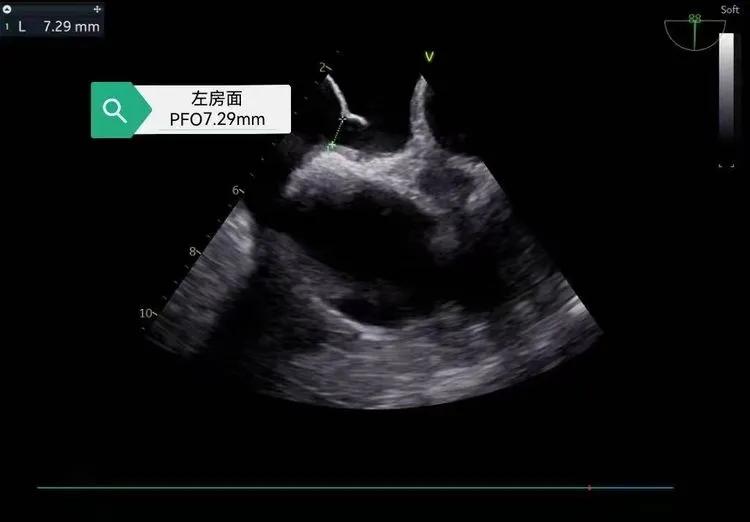

45岁的程先生5年内两次发生脑梗塞,心脏食道超声检查为这一异常状况锁定了病因——卵圆孔未闭,即心脏左右心房之间存在一道未闭合的“缝隙”。

安康市中医医院副院长、心血管专家沈桂冬介绍,卵圆孔未闭可形成心房异常血流通道,当潜在开放直径大于4mm时,血栓形成风险显著升高。咳嗽、用力屏气等动作导致右心房压力骤增时,血栓可能经该通道进入左心系统,进而堵塞脑部血管引发脑梗。

修补这个特殊的“心漏洞”,对医疗团队是不小的挑战。程先生心脏的卵圆孔缝隙并非固定尺寸,会随心脏舒张与收缩,在2mm至7mm之间变化,远超临床常见的2-4mm封堵范围。如何在封堵这一大型卵圆孔未闭的同时,不影响心脏正常结构,成为手术的核心难点。